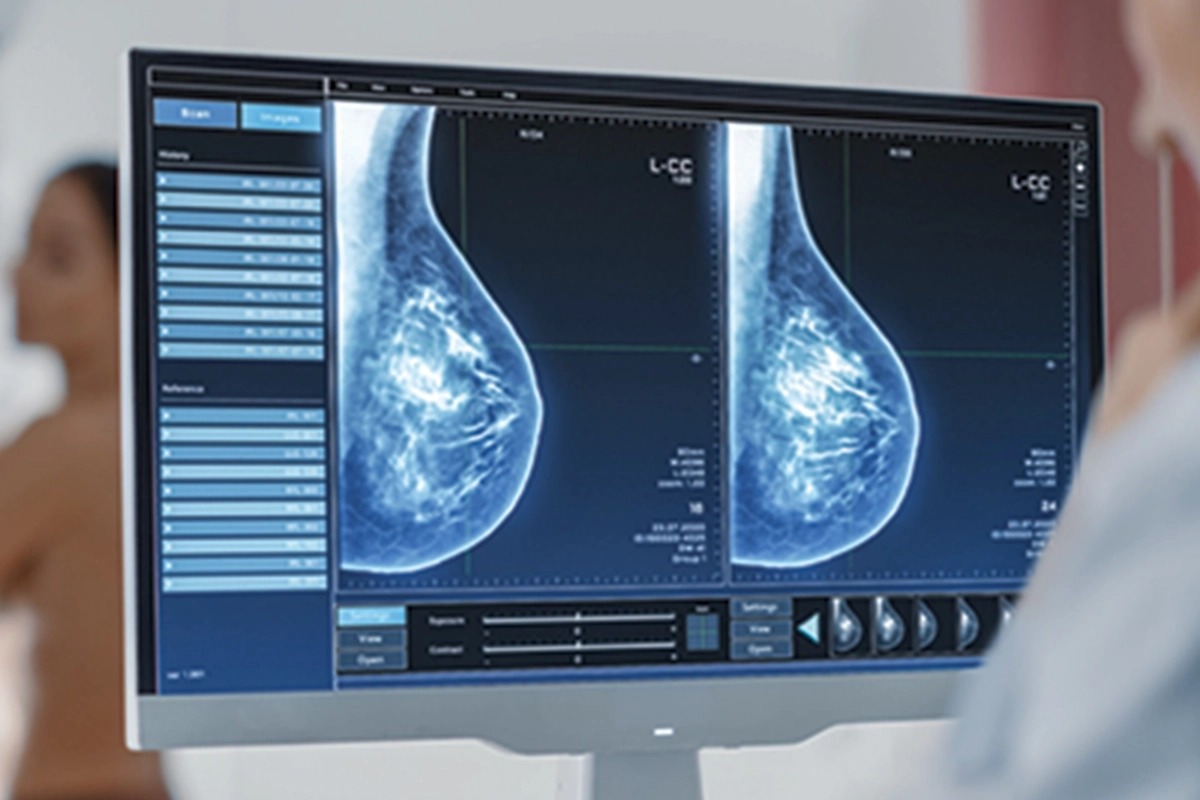

“Mamografi erken tanı ve tedavi için önemli”

Meme kontrolünün nasıl olması gerektiğini anlatan Poçan, “Memedeki problemleri tespit etmek için yaş fark etmeksizin, kendi kontrollerimizi aksatmamalıyız. Kontrollerde bir problem tespit ettiğimizde ya da kırk yaş üstünde ise bir hekim tarafınca kontrol, meme ultrasonu, gereklilik halinde mamografi veya meme MRG ile tetkikleri gerekmektedir. Ülkemiz sağlık politikalarınca mamografi ön planda tutulsa da teknolojik gelişmelerin ultrason cihazlarında yapmış olduğu belirgin gelişim nedeniyle meme ultrasonu ile değerlendirme hem güvenilir hem de değerlidir” dedi.

Meme Ultrasonu, Mamografi ve Meme MR’ı hakkında da bilgiler veren Dr. Poçan, “Her üç yöntem de meme kanseri taramasında önemli rol oynar, ancak uygulama durumuna, hastanın özelliklerine ve risk faktörlerine göre tercih edilir” şeklinde açıklamalarda bulundu.